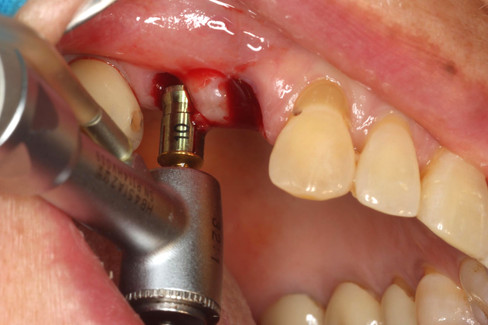

S-reamer with a 10mm stopper used at site #15 to safely control the depth during crestal sinus elevation.

The initial osteotomy was performed using a ø2.2 twist drill as the first step in the sequential drilling protocol.

Final osteotomy performed with a ø3.5 twist drill in preparation for placement of ø4.5 ALX fixture.

Bone density: D332

Fixture size: ALXIT 4510 30

Bone density: D333

Fixture size: ALXIT 4512 30

Scan bodies were placed on both implants for intraoral digital scanning on the day of surgery.